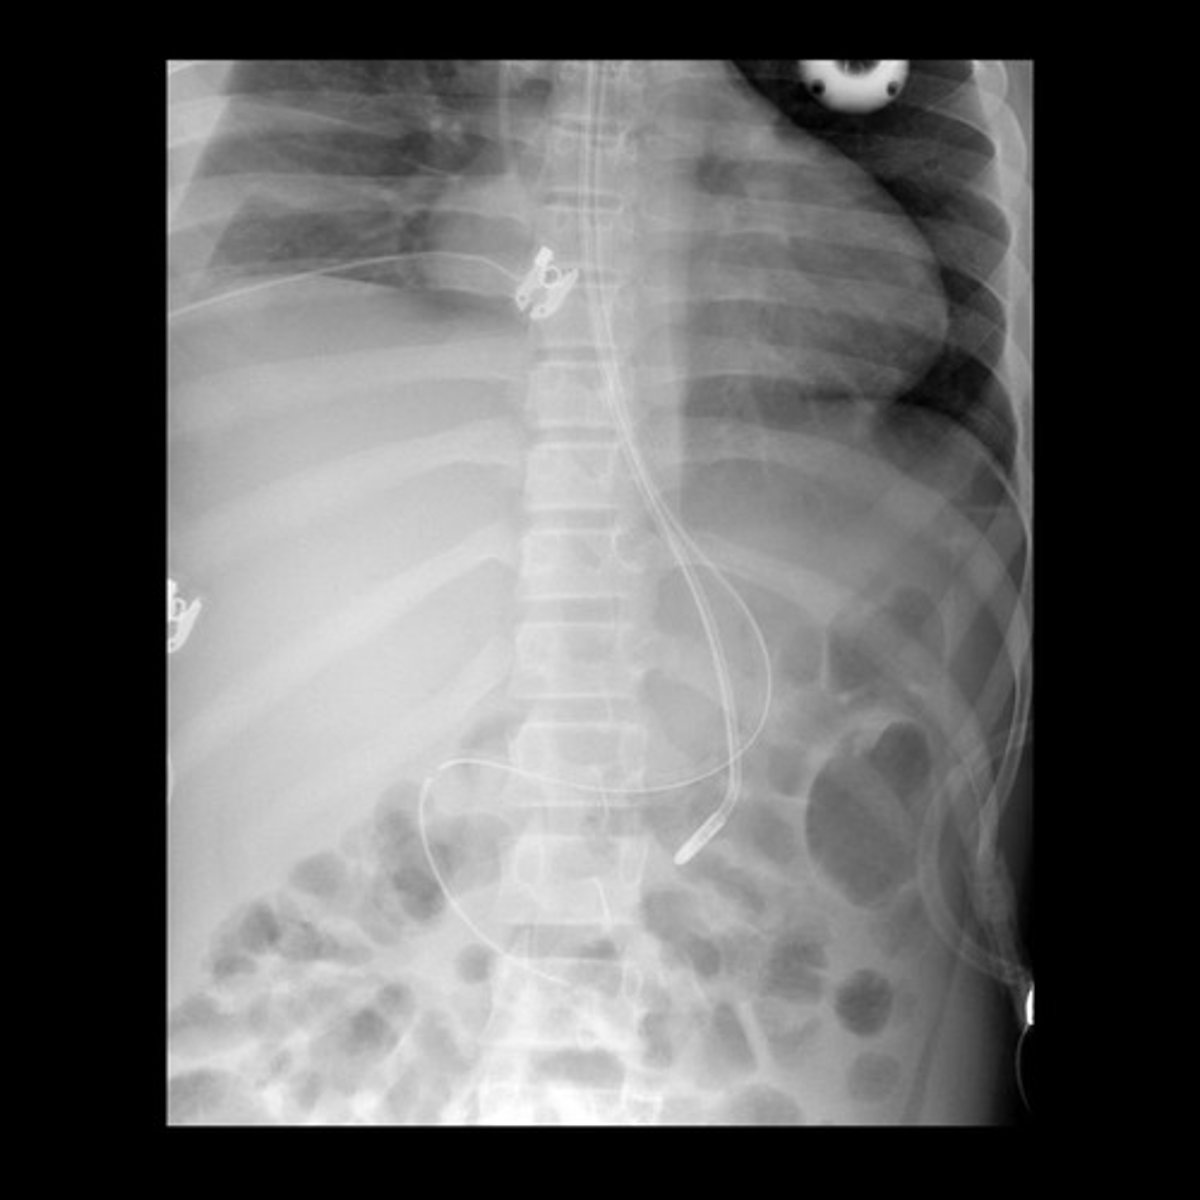

What are nasogastric tubes (NG) (HINT: 2)? Where are they inserted from and to? Name 1 type.

- Aids in removal of gastric contents and air in the stomach, and administers feedings/medications to patients who cannot swallow safely

- Inserted through nasopharynx or oropharynx into stomach

- Types: Salem-Sump, SBFT, Dobhoff tube